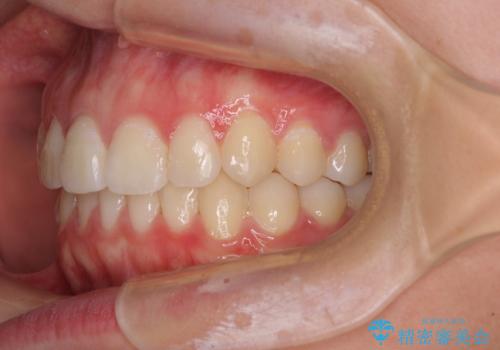

前歯のデコボコを改善 インビザライン矯正

- 口元のデコボコを気にして来院された患者様です。

前歯の捻れにより口元が閉じにくくなっていたため、歯列全体の側方への拡大と、歯と歯の間を少し削ってスペースを獲得することとしました。

ゴムかけをしっかりと行ってもらい、スッキリとした口元に仕上げることができました。